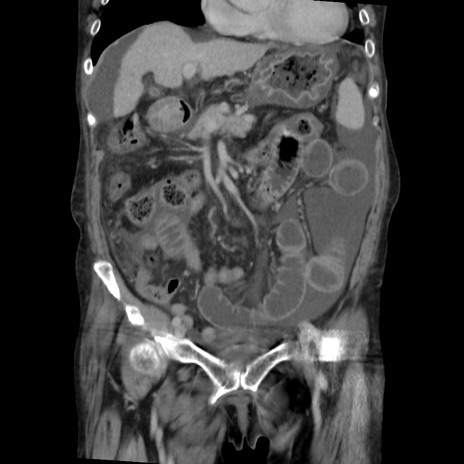

症例31(冠状断像)

【症例】80歳代 女性

【主訴】腹部膨満感

【現病歴】他院にて肝硬変にてフォロー中。1週間前から便秘、腹部膨満感、臍部腫瘤あり受診となる。

【既往歴】肝硬変

【身体所見】腹部膨隆あり、皮膚変化なし、疼痛なし。

【データ】WBC 4600、CRP 0.25